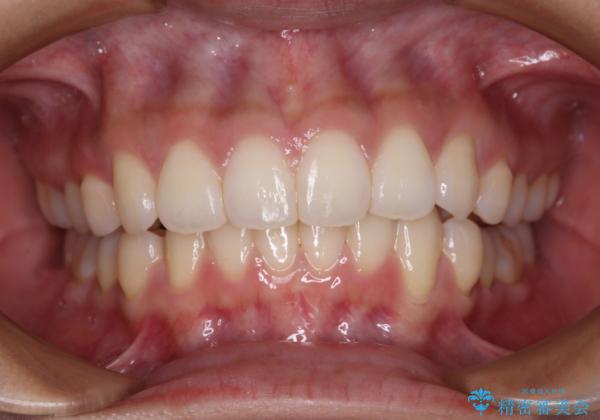

前歯のデコボコを解消 インビザラインの矯正治療

- 前歯のデコボコを治したいとのことで来院された患者様です。

上下顎ともに歯列全体の後方移動とIPR(歯と歯の間を削る)によってデコボコが解消するように設計し、インビザラインにより治療を行うこととしました。

上下ともにIPRを積極的に行っているため、舌の突出癖をしっかりと改善できないと、後戻りにより隙間やデコボコが早い段階で発現することになるため、舌のトレーニングが非常に大切になります。